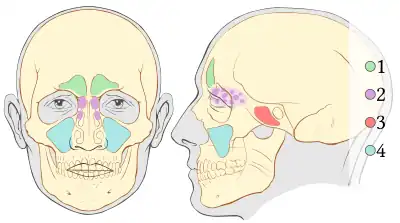

Nasennebenhöhle

1. Stirnhöhle (Sinus frontalis) (grün)

2. Siebbeinzellen (Cellulae ethmoidales) (lila)

3. Keilbeinhöhle (Sinus sphenoidalis) (rot)

4. Kieferhöhle (Sinus maxillaris) (blau)